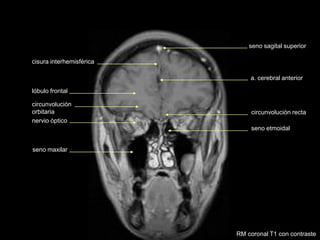

seno etmoidal

circunvolución recta

a. cerebral anterior

seno sagital superior

nervio óptico

seno maxilar

lóbulo frontal

circunvolución

orbitaria

cisura interhemisférica

RM coronal T1 con contraste